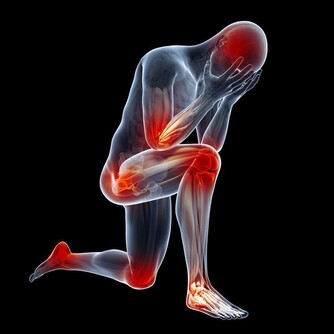

5關節痛

每天早上起床後吃幾片生薑或者煮姜棗水喝,一日3次堅持吃能明顯緩解關節的疼痛。